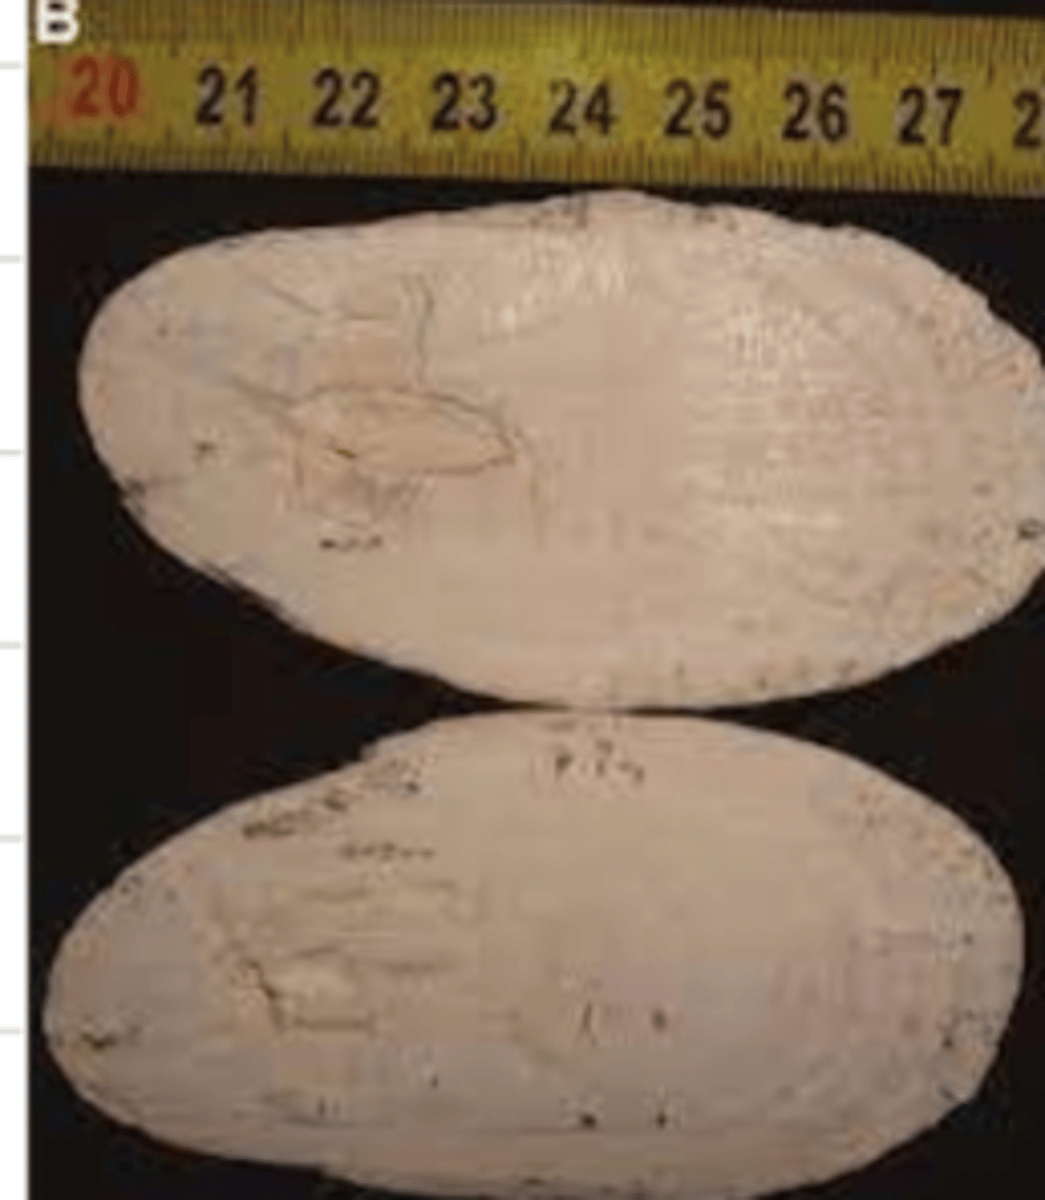

sialolith- a salivary gland stone

in the middle, it is a vegetable that has accumulated calcium carbonate around it

what is this?

it occurs when a piece of food gets stuck and then calcium carbonate deposits and accumulates around it. it might also be caused by the desquamation of cells

why might a horse have sialolithiasis?